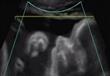

أشعة ''4D'' توضح كيفية تعايش الجنين داخل رحم أمه